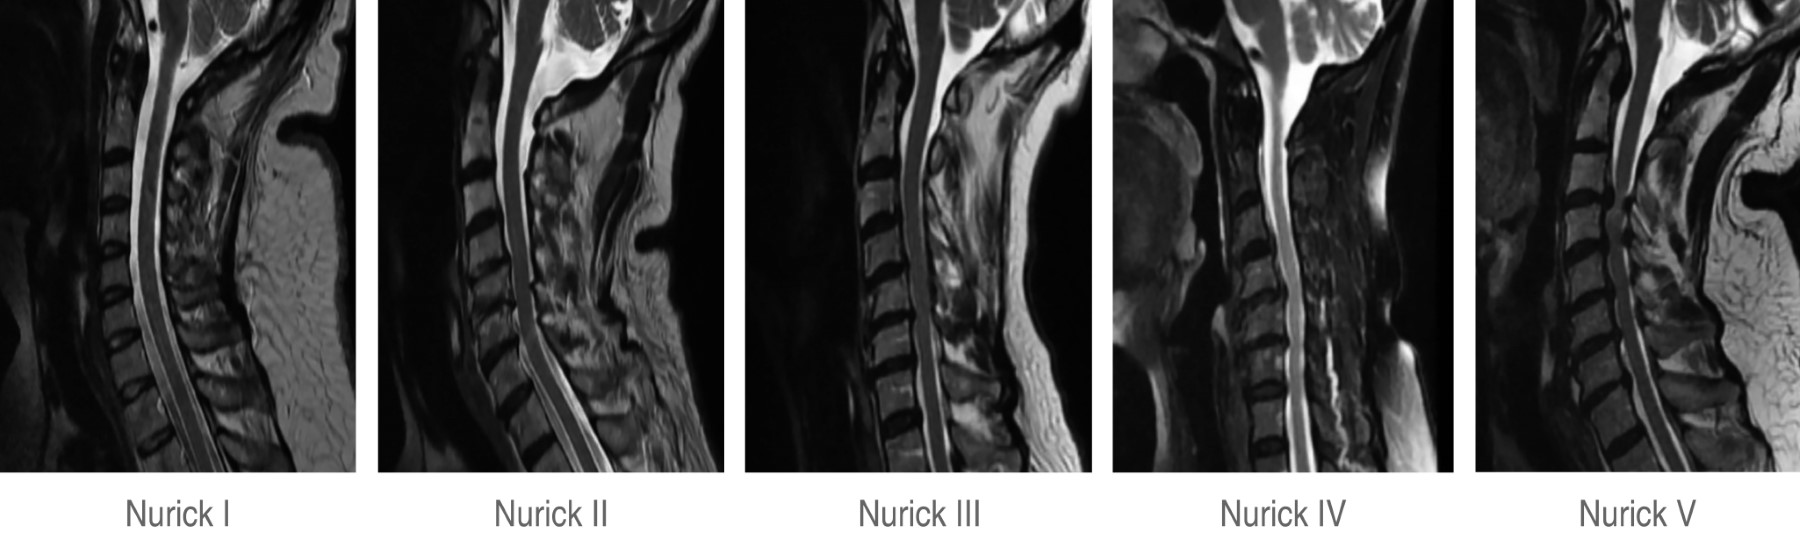

Para establecer un diagnóstico se debe realizar un examen clínico y documentar cambios radiológicos de afectación medular, de igual manera se pueden hacer mediciones con el uso de tomografía o resonancia magnética, los cuales son estudios costosos y no siempre accesibles para toda la población. Es por ello que la construcción del diagnóstico puede complementarse con la escala de Nurick, el Cuestionario de Evaluación de Mielopatía de la Asociación Japonesa de Ortopedia (JOA, por sus siglas en inglés) y estudios de imagen, dentro de los cuales la resonancia magnética es el estándar de oro (Figura 1).7

Se reclutaron a 79 participantes, de los cuales 39 (60.9 años en promedio, 56.4% del sexo femenino) presentaron mielopatía espondilótica asociada a estrechez del CMC y 40 fueron controles (57.9 años en promedio, 82.5% de sexo femenino) con diámetro de CMC dentro de parámetros normales, sin presentar diferencia significativa por edad. Los pacientes con estrechez de CMC presentaron una clasificación promedio de 2.74 ± 1.51 en escala de Nurick.